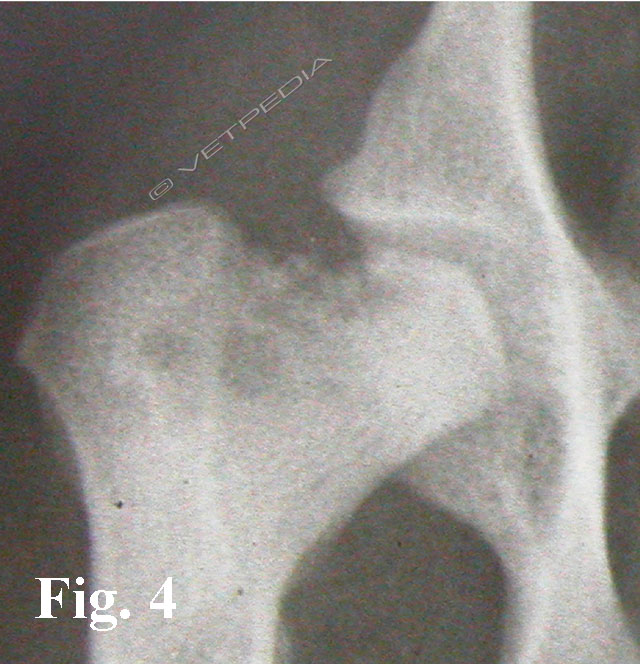

{{/_source.additionalInfo}}La necrosi asettica della testa del femore è anche denominata malattia di Legg Calvè Perthes e necrosi avascolare della testa del femore. Si tratta di un'affezione ortopedica coinvolgente l’articolazione coxofemorale di cani di razza toy o di piccola taglia durante il periodo dell’accrescimento, ad interessamento più frequentemente monola